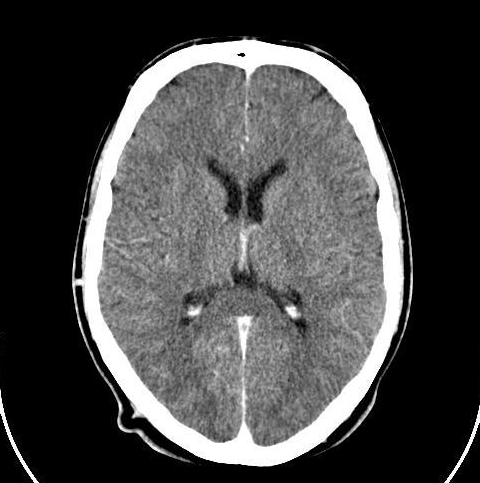

Most people think of the liver as just a filter.

But it's actually your body's most sophisticated chemical processing plant.

It holds 13% of your total blood supply at any moment.

And what it does with that blood determines how how you feel & function.

Your liver receives blood from 2 sources:

1. The hepatic artery brings oxygen-rich blood from your heart

2. The portal vein delivers nutrient-rich blood straight from your intestines

Inside your liver, this blood flows through a marvel of biological engineering: Image

2 main lobes, divided into 8 segments, containing over 1,000 tiny processing units called lobules.

Each hexagonal lobule is a microscopic factory working 24/7.